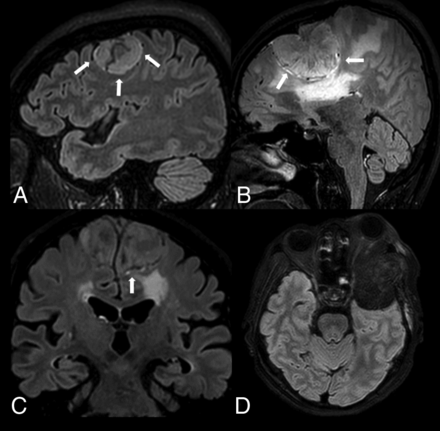

First, we evaluated the MR imaging findings including signal intensity on T2WI, dural tail (absent or present), osseous destruction (absent, marrow edema, cortex disruption, or cortical breakthrough), and hyperostosis (absent or present) on T2WI and CE-T1WI sequences. Then we defined the characteristics of rim enhancement at the tumor-brain interface as a rim with relatively high signal intensity on CE-FLAIR. We graded the rim enhancement patterns from 0 to 3 by their extent as 0, no rim visible; 1, 50% rim visible; 2, >50% rim visible but <100%; and 3, complete rim enhancement of the tumor-brain interface (100%) (Fig 1). There was no apparent discrepancy in demonstrating rim enhancement on CE-3D FLAIR images between 1.5T and 3T scanners by observation. Additionally, we evaluated leptomeningeal enhancement (absent or present) and graded peritumoral brain edema (0 to 2), which was defined as 0, no edema; 1, edema <2.0 cm radially from the tumor; and 2, edema ≥2.0 cm radially from the tumor. On CE-T1WI, we defined the contrast-enhancement pattern of the tumor as homogeneous or heterogeneous. Any discrepancies in interpretations of MR imaging findings were resolved by consensus.

Four different rim-enhancement patterns at the tumor-brain interface on the CE-FLAIR sequence (arrows). A, Complete rim enhancement (CE-FLAIR rim sign). B, Rim enhancement of ≥50% but <100%. C, Rim enhancement of <50%. D, No visible rim enhancement. The pathologic results of A, B, and C are meningioma, and D is plasmacytoma.